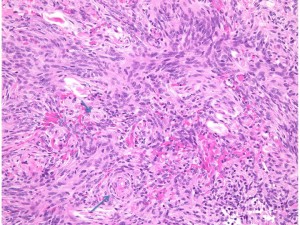

atypical meningioma WHO grade 2(長嶋和郎先生の病理教室)

高齢者の後頭窩 (ptrous ridge) にみられた大きな髄膜腫でした。meningiomaと考えられますが、whorl patternやmeningothelial featureなど特徴的なpatternが見られずpattern lessと見做されます。さらに、腫大しchromatinに富む核が見られ、異型細胞と考えられます。

EMAが陽性となることでmeningiomaが示唆されます(左:EMA染色 x200x)。腫瘍の一部でcollagen fiberの多い組織に移行し、核の消失を伴う壊死性変化を示す部位が見られます。

腫瘍の周辺部にonion bulb構造 (→)が見られ、meningiomaの診断が妥当です(左)。細胞核の異型性がありMIB-1 indexが10%と高値であり(右)、atypical meningiomaです。